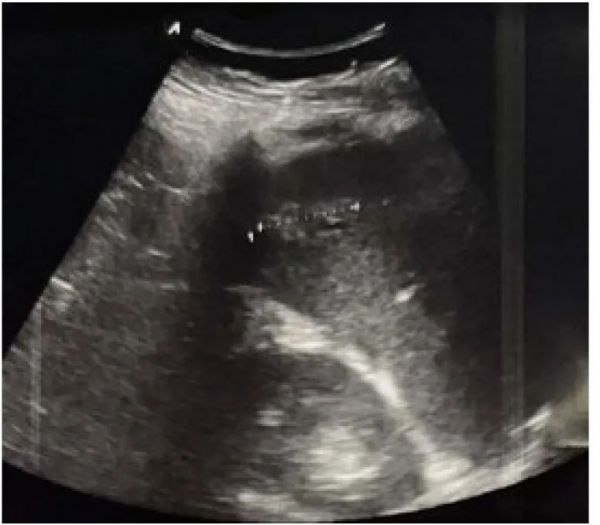

除体格检查外,在创伤集中评估中,使用创伤超声检查(FAST)在临床上评估腹腔积血也非常重要,同时它提供额外的腹部无创检查,同时对复苏工作的干扰最小[33]。此外,它可以在创伤部位或在患者运输过程中进行。它对诊断游离液体具有高特异性(99%),但敏感性也较低(60-80%),因此不能排除游离液体[34]。在创伤患者中,FAST可以快速进行,如果最初为阴性,则可以根据需要根据患者的临床状态重复进行。另一方面,如果为阳性,并且存在出血性休克,则提示腹腔内出血以及需要手术或手术治疗[35]。主要问题是使用US可以看到的血量,这为计算机断层扫描(CT)检查提供了优势[36]。这可以解释为什么27-29%的经CT扫描检查证实的脾损伤患者没有美国可检测到的腹腔出血,以及为什么这种损伤很容易被遗漏[33]。应该强调的是,在创伤中,实体器官损伤可以用FAST(图 2),但前提是它不耗时且不会干扰复苏。不幸的是,在这种情况下,检查的敏感性较低(41-44%),因为新鲜凝固的血液与受损实体器官的实质具有相似的回声性[34]。

图 2脾外伤(高回声灶直径31.2毫米)。